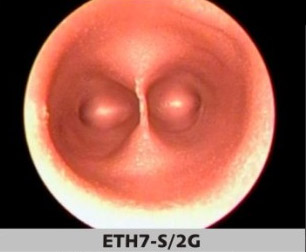

ETH Artıfıcıal Uterus

Dünyanın önde gelen jinekologlarının gözlemlerine göre tasarlanan yapay uterusun patolojileri, vajinal histeroskopide eğitim için, tortuoz serviksin değerlendirilmesi, tanı muayeneleri, biyopsi gibi işlemler, yabancı vücut yapılarının çıkarılması, myomlar, polipler, uterin yanlış biçimlerinin değerlendirilmesi ve düzeltilmesi ve daha birçok işlemin gerçeklemesini sağlar.

Yapay uterusun farklı pataloji seçenekleri ile belirli eğitim amaçlarına olanak sağlamaktadır.

Histeroskopi eğitim simülatörü ile birlikte kullanılmaktadır.